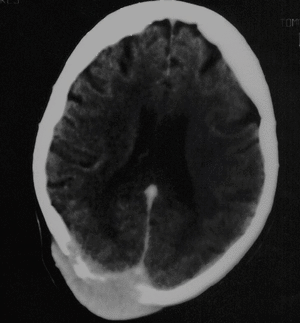

Se observan en las imágenes lesiones osteolíticas en región frontal medial, parietal izquierda y parietoocipital derecha, teniendo en esta última localización tejido sólido suprayacente (figs. 1 y 2). Esta lesión sólida parece erosionar todo el diploe y ambas tablas interna y externa, y extenderse al espacio epidural y muy probablemente invade el seno sagital superior. Esta lesión capta contraste.

Fig. 1.